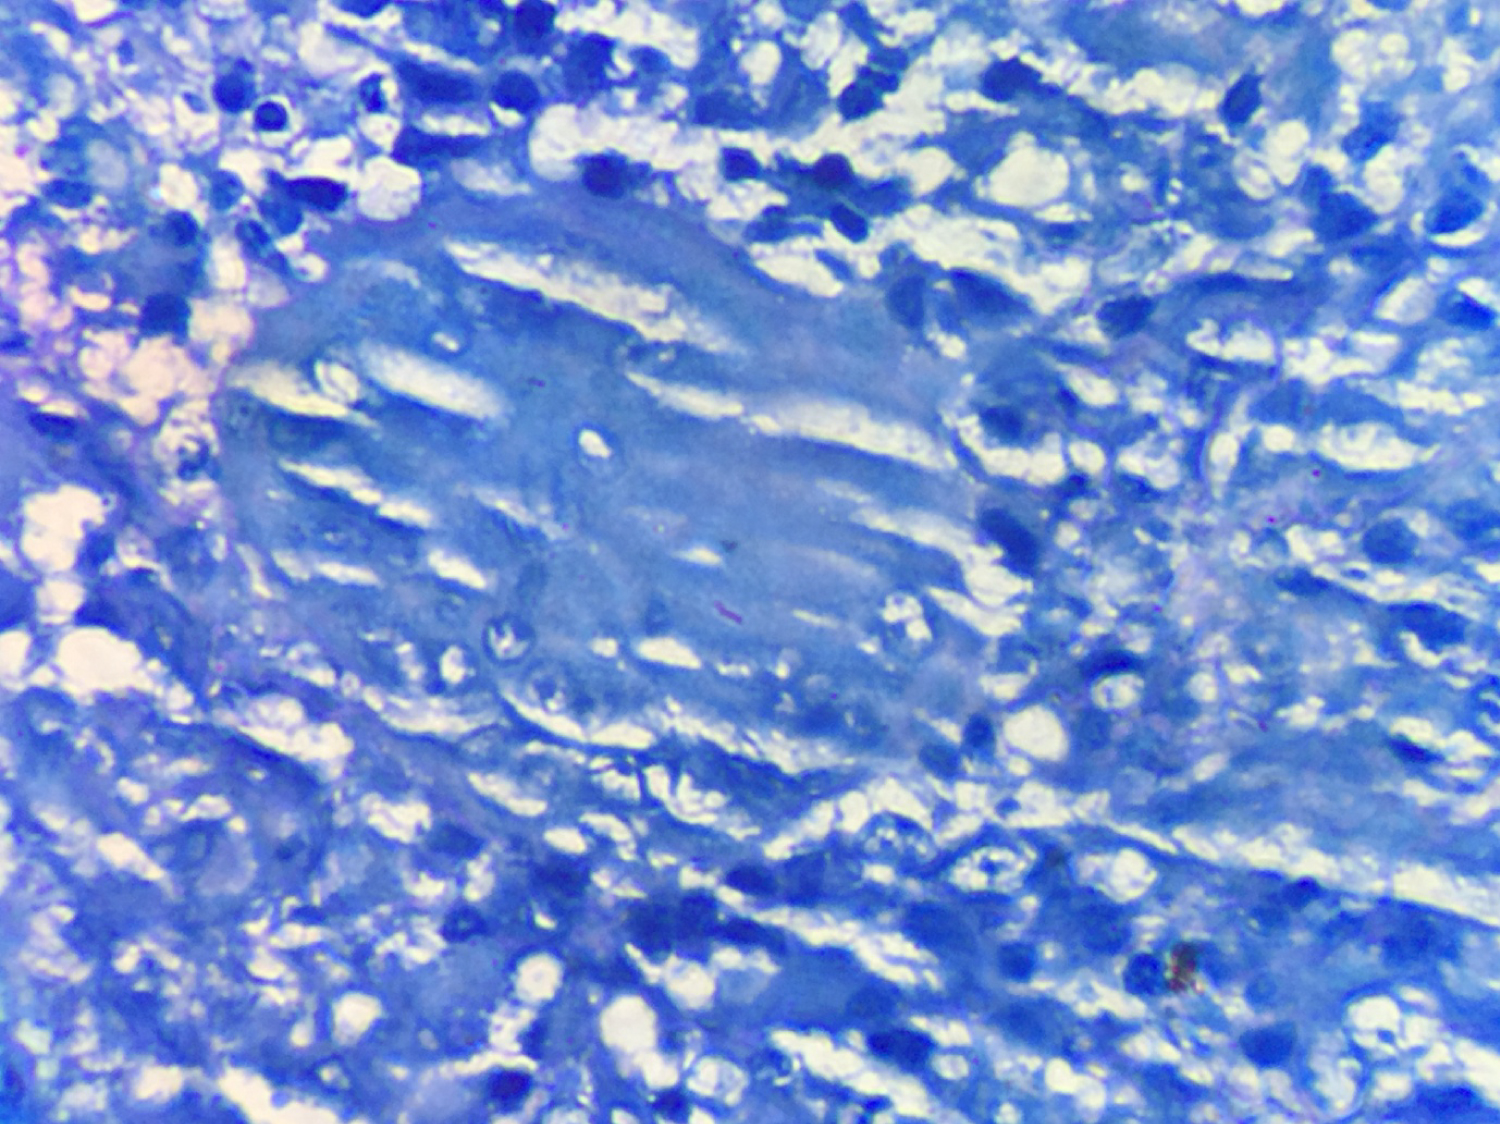

She was managed as a case of Tubercular Lymphadentits with ANCA mediated focal necrotising crescentic glomerulonephritis. She received alternate days of plasmapheresis with 0.4 L/Kg of plasma removed in each session, for a total duration of five sessions and Inj Methyl prednisolone of 500 mg for three days followed by oral prednisolone at 01 mg per kg body weight. Anti-tubercular therapy in the form of cap Rifampicin, Tab Isoniazid, Tab Ethambutol and Tab Pyrazinamide was initiated after her plasmapheresis sessions were finished. She was also treated with low monthly dose of injection Cyclophosphomide of 500 mg IV. There was rapid improvement in her clinical condition and urine output as a result of this regime. After two weeks post-initiation of plasmapheresis, her serum creatinine settled to 1.9 mg/dl. Her steroids were rapidly tapered in view of her active tuberculosis and low dose Inj Cyclophosphamide 500 mg IV, was continued every 02 weeks for three months; followed by maintenance therapy with tablet Azathiopyrine at 01.5 mg/Kg body weight. She had good response to her antitubercular regime and a repeat CT of the chest and abdomen at two months, revealed marked resolution of her lymph nodes in the retroperitoneal region and was shifted to the three drug maintenance regime and her Tab Pyrazinamide was stopped. At six months, follow up p-ANCA returned negative. She was continued on anti-tubercular therapy for nine months. She received maintenance therapy for her necrotic crescentic glomerulonephritis with Tab Azathiopyrine for a period of 24 months. Presently she is on regular follow-up and maintaining stable creatinine of 1.7 mg/dl with resolution of her Tubercular Lymphadenitis (Figure 1, Figure 2, Figure 3 and Figure 4).

Figure 4: ZN stain showing acid fast bacilli. View Figure 4